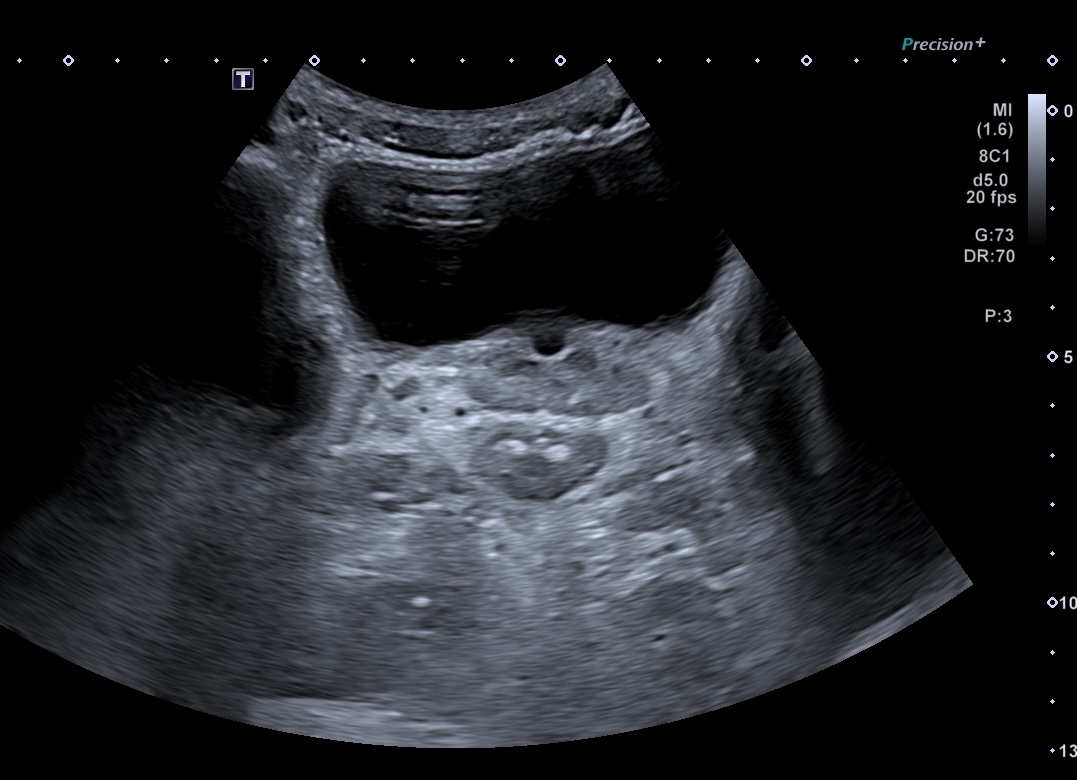

Maladie de Crohn, rectum (épaissisement asymétrique prédominant à la partie postérieure) coupe passant par la prostate

Même patient coupe longitudinale

Epaississement asymétrique prédominant partie postérieure (9 mm)